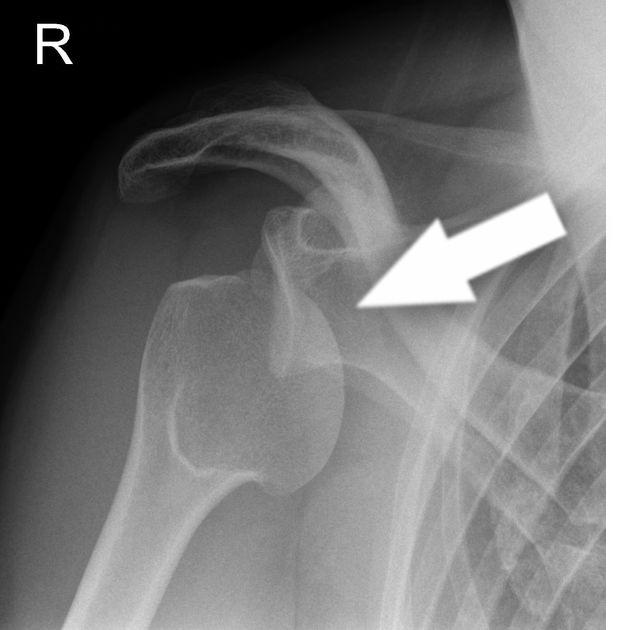

Shoulder dislocation is a common injury where the upper arm bone is displaced from the shoulder socket. These most often occur from a traumatic injury such as a direct blow to the shoulder. The soft tissues around the shoulder can be stretched during the injury and can take some time to heal.